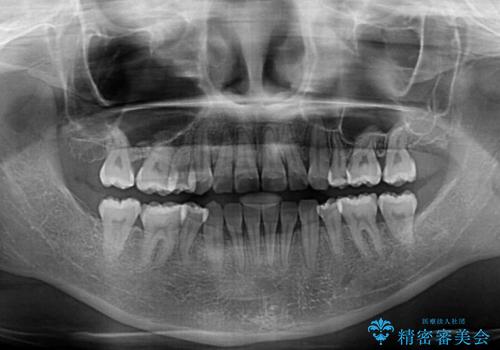

重度叢生と埋もれた奥歯 8本を抜歯したワイヤー矯正

- 内側に生えている歯や埋もれた奥歯を気にして来院された患者様です。

顎の骨が小さいため、歯列が収まりきらずに叢生や未萌出となっている状態でした。

埋もれた奥歯を萌出させ、さらにデコボコを解消するために、上下左右の第1小臼歯4本に加え、親知らず4本も抜歯し、ワイヤー装置にて矯正治療を行うこととしました。

親知らずの抜歯により埋もれた奥歯周辺の歯肉が切除され、矯正装置が装着できるようになりました。

奥歯の移動、特に下顎大臼歯の移動は時間がかかることが多く、3年以上の治療期間を想定していましたが、想像以上に動きがよく、2年強で終えることができました。